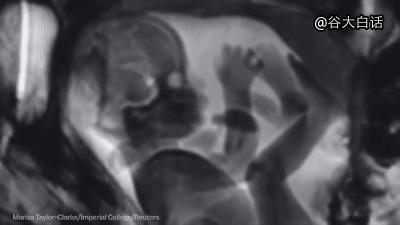

#爱你爱到骨头里#【MRI下诡异而奇妙的人体】这是一段用核磁共振成像技术制作的动态短片,将人类喝水、亲嘴、嘿咻、拉翔、生娃、说中文、说德文等日常活动展现得毫纤毕现、一览无遗。doge微猎奇,微暴,慎点。